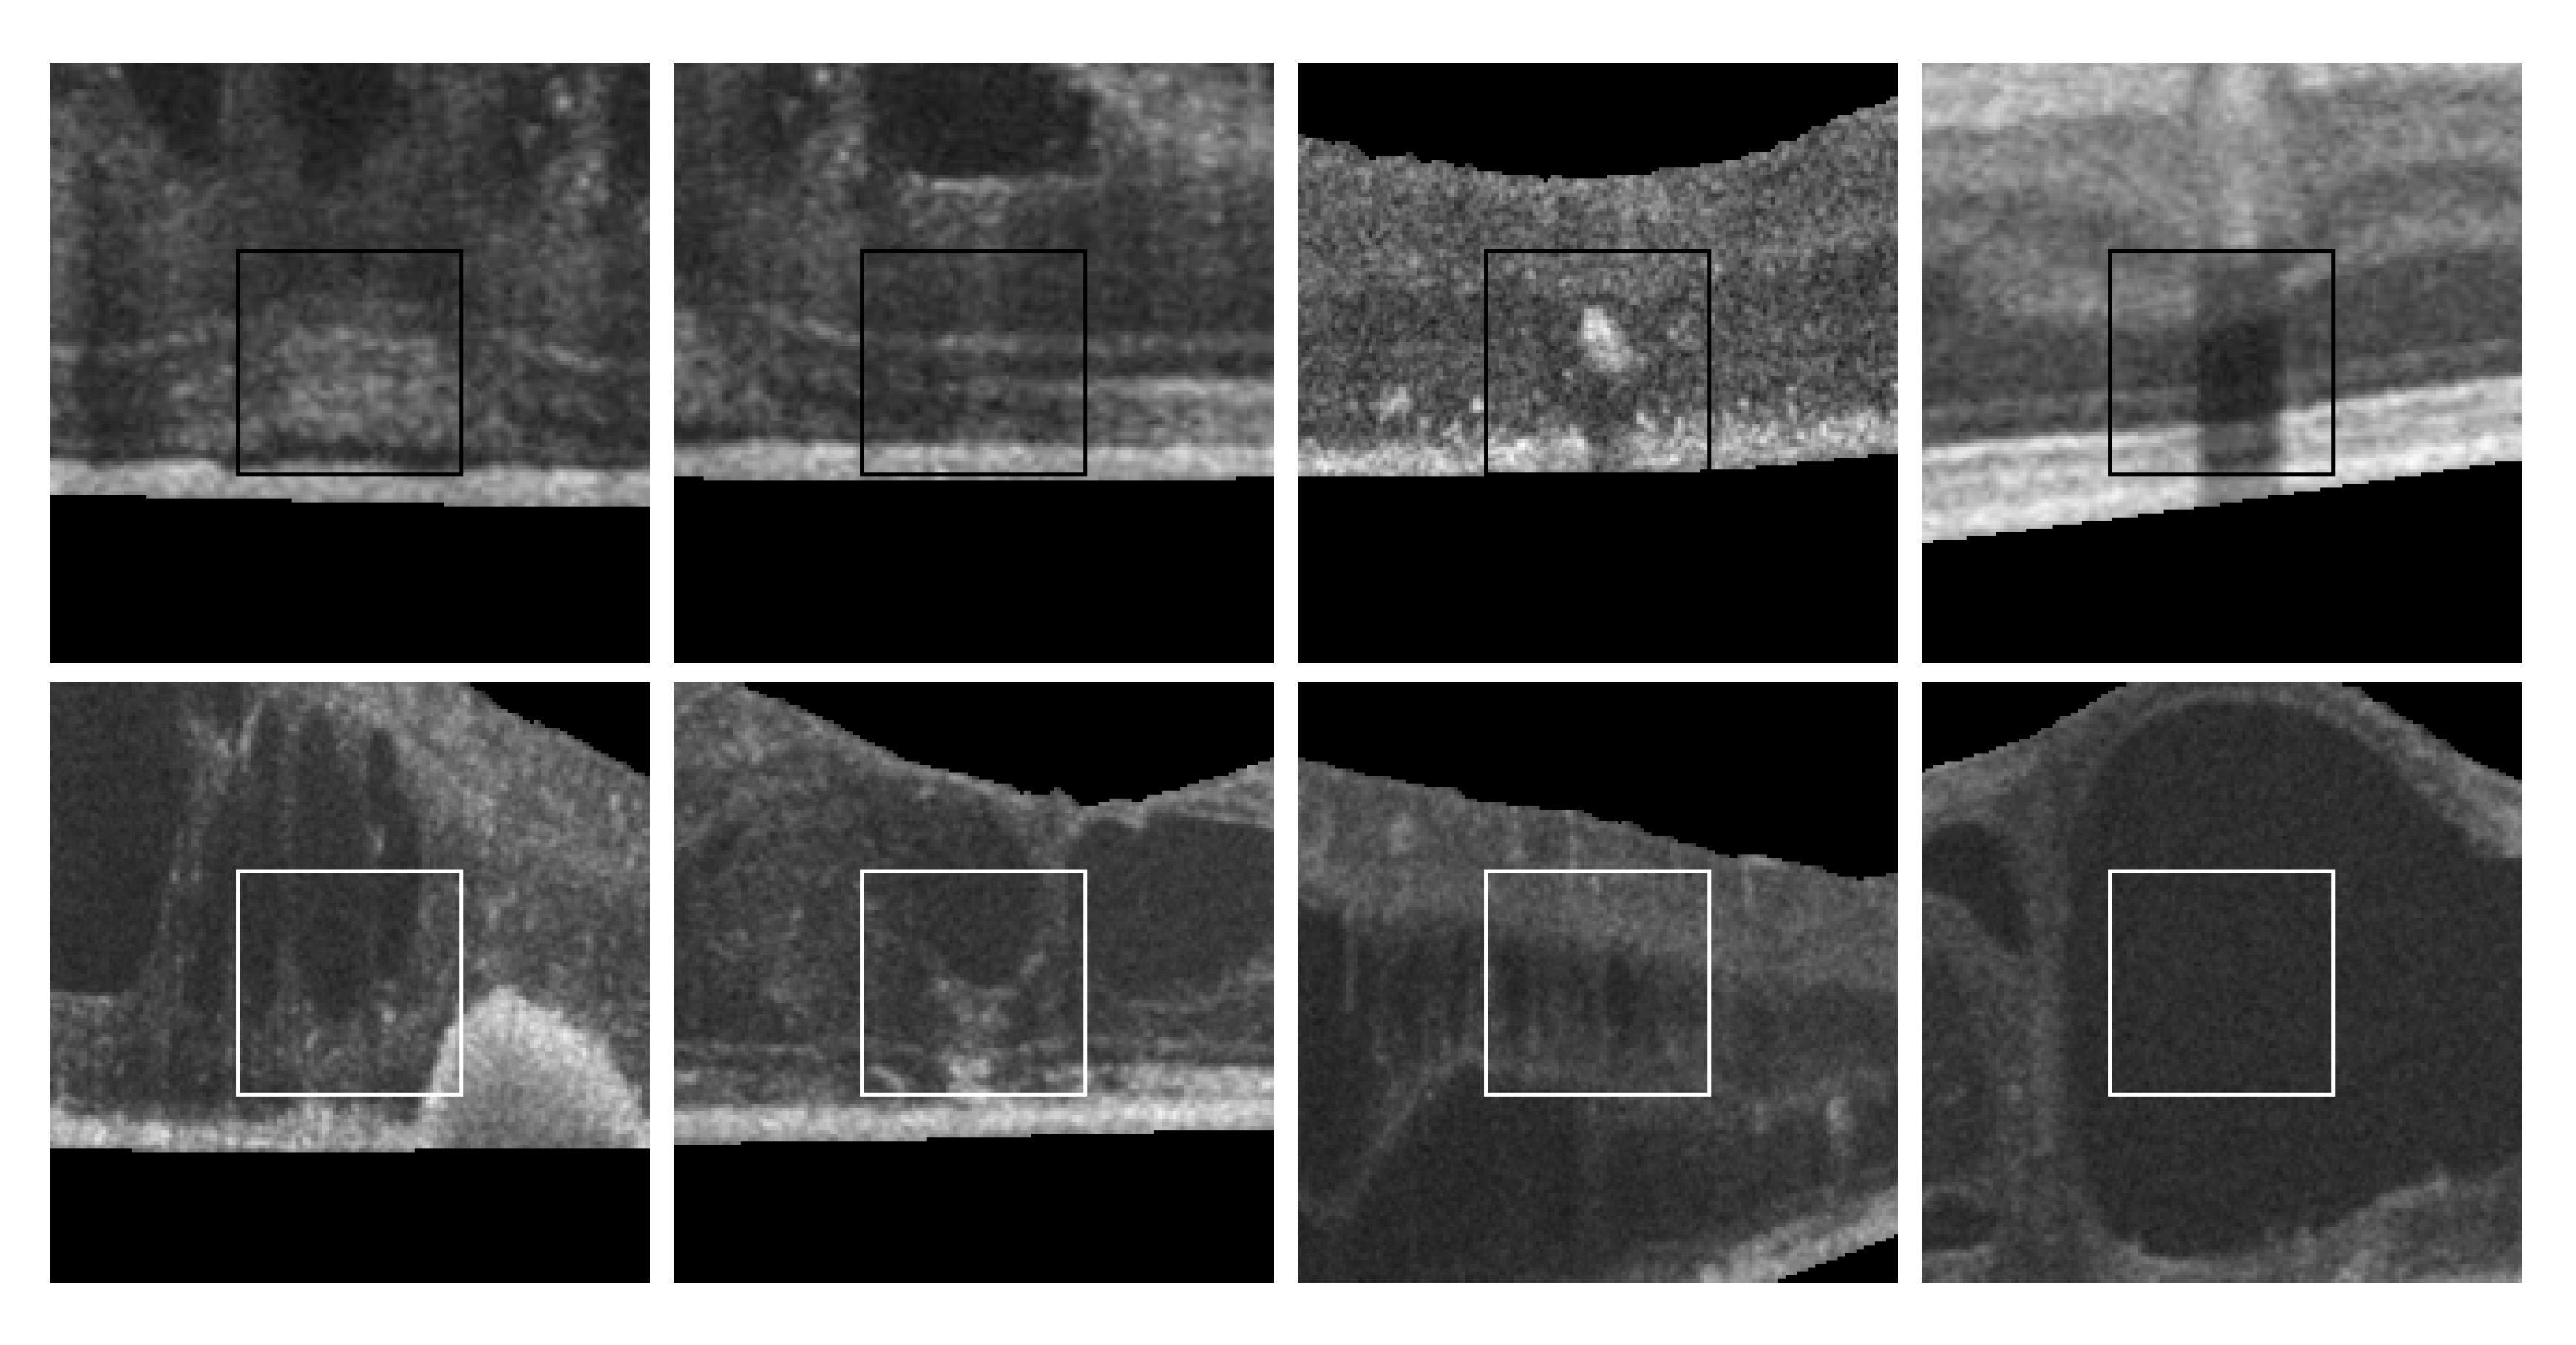

Finally, as shown in Figure 2, 2nd row, not all cysts have a precise border that can be segmented. Many times, these fluid regions can be clearly distinguished inside the retinal layers thanks to a significant contrast between the internal fluid and the surrounding neighboring tissues (as the examples of Figure 2, 1st row show). In these cases, a segmentational approach can produce acceptable results. However, many other times this process is not as simple as the previous ones. In other cases, cysts do not present enough contrast, being extremely difficult to accurately identify their entire contour (Figure 2, 2nd row, (a,b)) or they may appear in nearby groups that make extremely complicated the identification of their limits (Figure 2, 2nd row, (c,d)). In these cases, a regional classification with the identification of the cyst presence is more feasible and also clinically relevant for the medical analysis and diagnosis.

Figure 2. Examples with accumulations of intraretinal fluid with adequate definition for a segmentation (1st row) and counter-examples with blurred, merged, and obfuscated edges that are hard to segment precisely (2nd row). (a,b) Individual cystoid fluid bodies. (c,d) Groups of fluid accumulations.